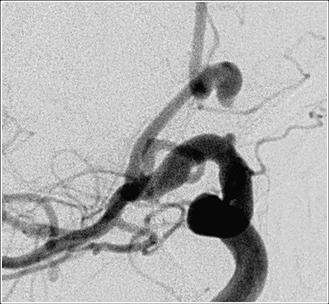

Endovascular occlusion of aneurysms includes the use of detachable coils. This is a angiographic procedure where a small soft catheter is introduced into the blood vessel from the leg artery. From there the catheter is carefully threaded up into the brain and the tip of the catheter is placed in the aneurysm (figure 6). Then through the catheter small soft coils are introduced into the aneurysm to block it completely (figure 7).

Figure 6. The catheter is carefully threaded up into the brain.

Figure 7. Endovascular occlusion of aneurysms includes the use of detachable coils.